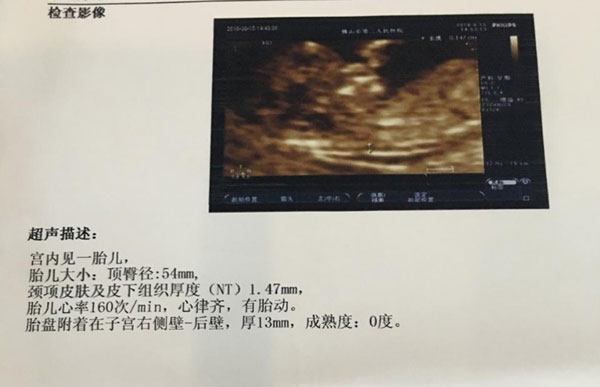

看了群里有宝妈说通过nt单子看男孩女孩很准,就如nt值和nt图片都是可以判断宝宝性别的。怀第一胎的时候也没有太注意nt单子,这二胎做了nt之后就开始研究,希望能从图片上找到关于怀男孩女孩的蛛丝马迹。有没有已生男孩的宝妈透露一下,当时怀孕时nt单子图片是如何的呢?

据了解,网传通过nt单子上的nt图片可以判断出男孩女孩,其根据nt截图中胎儿的姿势和脊柱线,得出的验证结果基本就十有八九了。据说如果nt图是弯着的生男孩,nt图是平行的话生女孩。弯着和平行其实参照点就是脊柱线这里,已生宝妈表示,一般脊柱线大于30度的生男孩的可能性比较大,反之小于30度的生女孩的可能性比较大。

通过nt单子上的nt图片判断男孩女孩还有个说法就是看尾椎骨这里,有的人说可以看到nub点,有的则说尾椎骨上翘生男孩,尾椎骨和身体呈现平缓的话生女孩。就nub,不少过来人表示男胎发育快一些,nub点也就是我们说的胎儿生殖器结节显现比较早,如果有一个凸出点的话就说明是胎儿的生殖器,由此凸起点判断是男孩是女孩。

其次就是尾椎骨上翘与否,据说上翘的怀男孩的几率大,这是因为男孩要发育内外生殖器,这个上翘姿势是在留下发育空间,而女孩发育不需要这么繁琐,一般都是平平的,比较平缓。这也应验了老一辈们的一个说法,儿靠女睡,意思也就是男孩一般都是靠着妈妈的,女孩一般都是睡在妈妈肚子里面的,大家可以仔细看下自己的nt图片。

在nt单子上除了根据nt图判断男孩女孩外,还有个地方就是nt值。一般nt值都是和nt图片一起结合参考的,这样的判断结果会更准。网传如果nt值大于1.5的话生男孩,小于1的话生女孩。过来人总结的说法是,正常范围内nt值偏高的男孩居多,偏低的女孩居多,这是因为男孩的皮肤要比女孩的皮肤厚一些的原因,因此nt值也要稍微高一点。